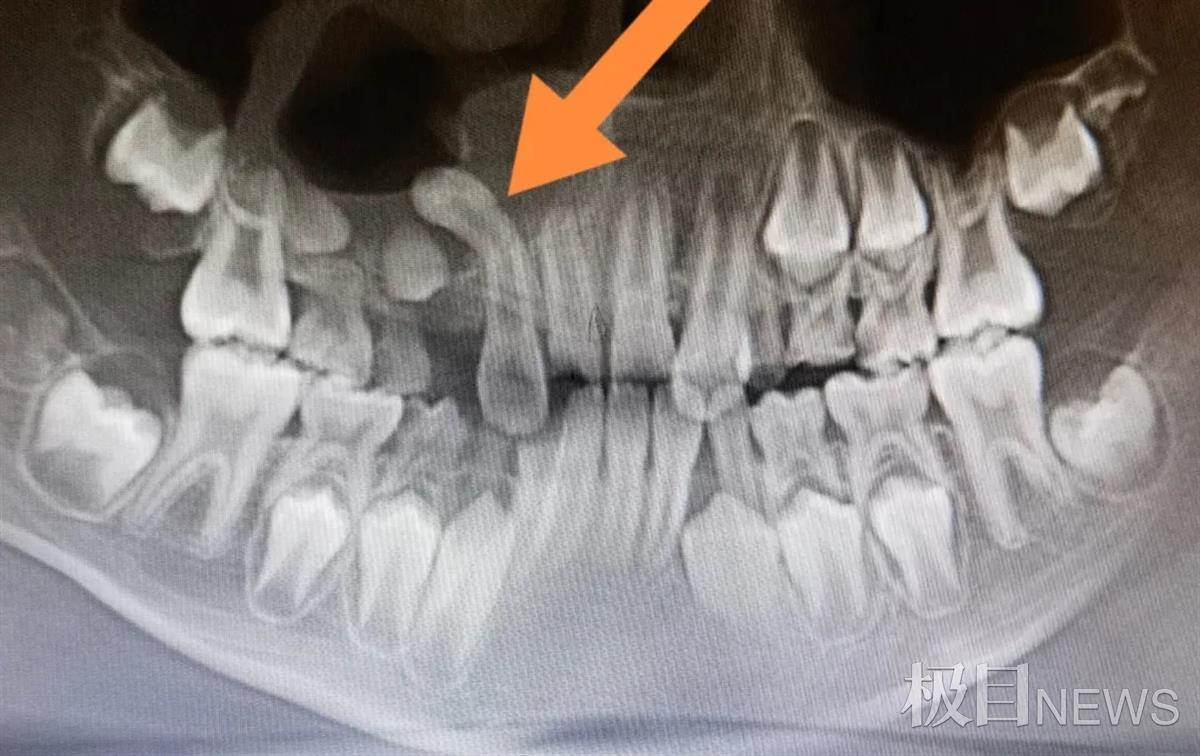

13岁男孩牙齿倒起长 "逆流而上"差点冲进鼻子

9岁男童多长一颗牙,180度倒置反转让专家直呼罕见

求助大家,尽头牙是倒着的,这种情况是不是必须拔掉

埋伏牙牵引一例